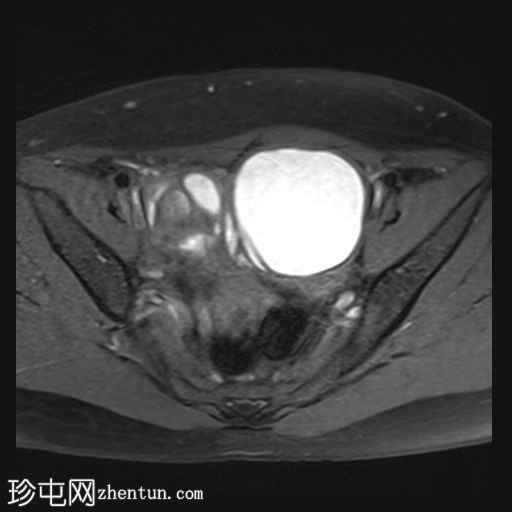

轴位

T2加权像

左侧卵巢可见一巨大、无强化囊性病变。该病变壁薄,在T1加权像和T1脂肪抑制像上呈均匀高信号,在T2加权像上呈独特的阴影状,符合子宫内膜异位囊肿的特征。值得注意的是,该病变可见两个增强灶,但未见内部实性成分或对比增强。

此外,右侧卵巢内数个小的、无强化囊性病变表现出类似的信号特征,这也符合子宫内膜异位囊肿的特征。

双侧卵巢向内侧移位,形成“接吻卵巢征”。

子宫后壁子宫圆锥增厚,累及直肠前壁。

子宫圆韧带增厚。

子宫、双侧卵巢和直肠因挛缩性粘连/纤维带而靠近,形成近期描述的深部盆腔子宫内膜异位症的“三叶草征”。

深部盆腔子宫内膜异位囊肿和双侧卵巢子宫内膜异位囊肿的检查结果令人印象深刻。